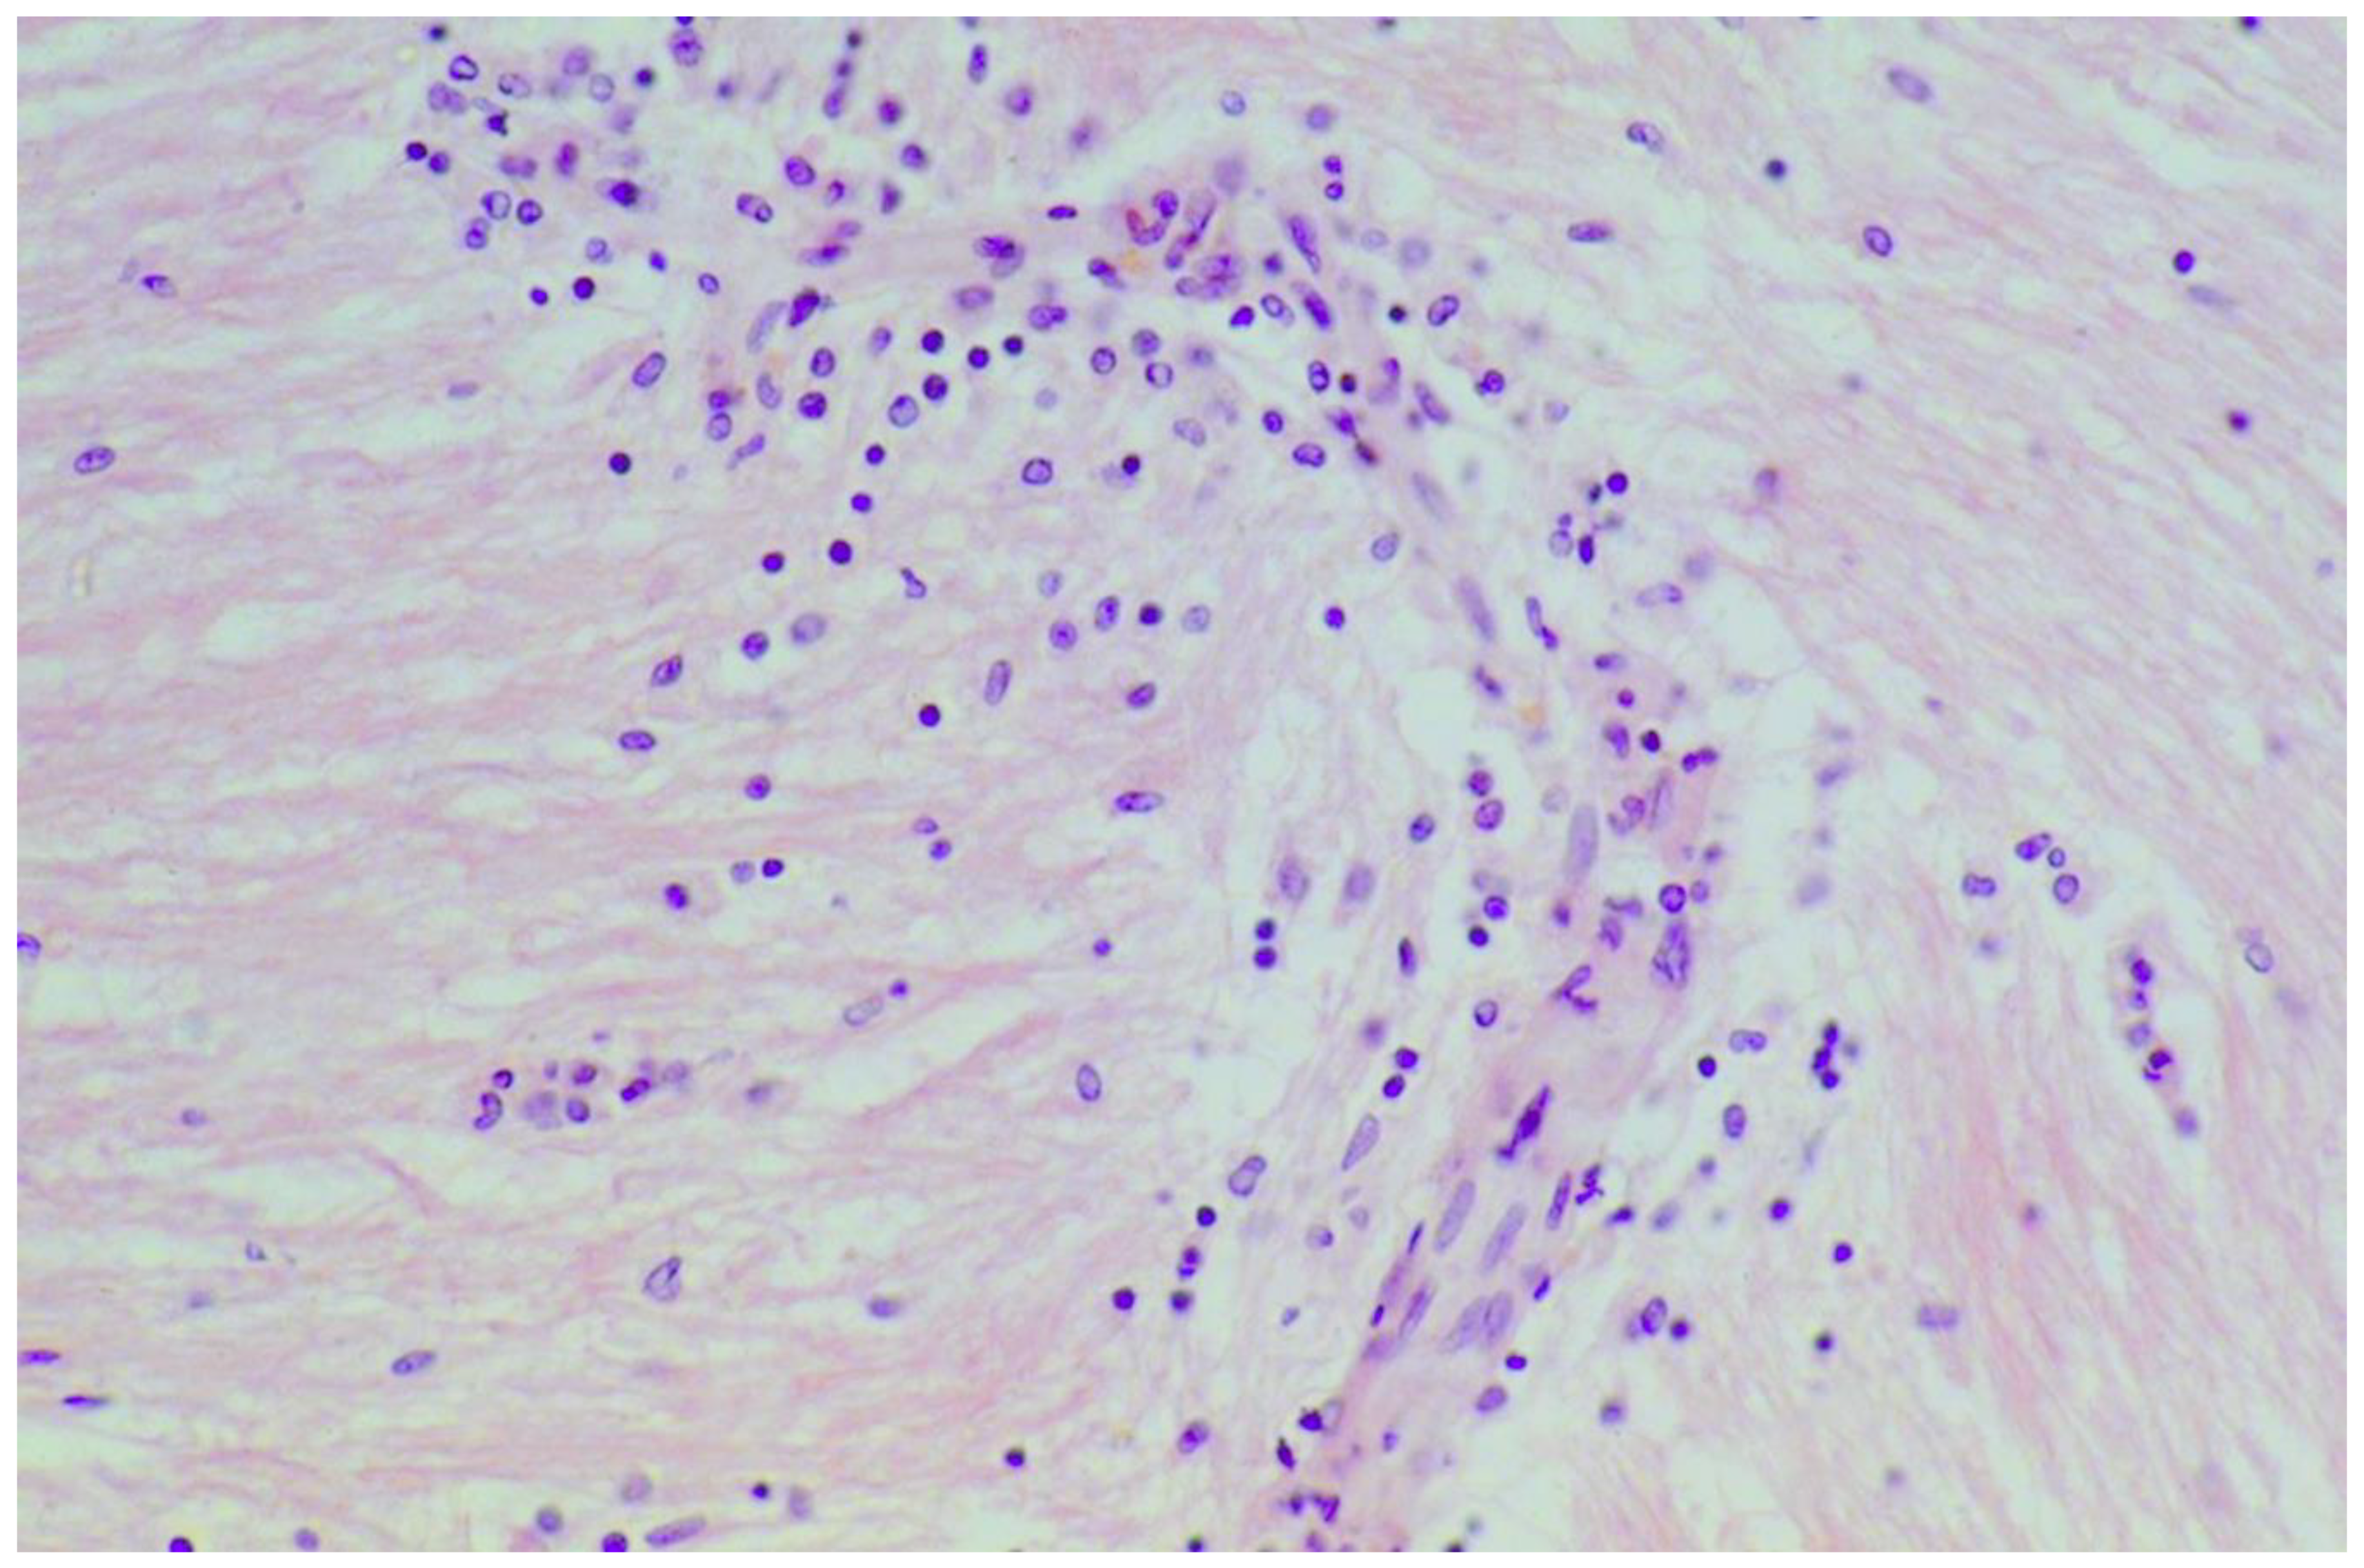

| Cooke 1966, UK (I) * | 11 | Nerve | Axonal swelling, loss of myelinated fibers, focal proliferation of sarcolemmal nuclei and collateral reinnervation |

| Chin 2003, USA | 3 | Sural nerve | Mild to moderately severe chronic axonopathy with loss of myelinated fibers |

| Hadjivassiliou 2006, UK ** | 3 | Sural nerve | Focal inflammatory cell infiltrate in the epineurium & perivascular cuffing of lymphocytes; Patchy loss of myelinated fibers & occasional degeneration |

| Simonati 1998, Italy | 1 | Sural nerve | Chronic axonal neuropathy; Significant loss of myelinated fibers & Schwann cell nuclei; Low density of unmyelinated fibers; No inflammatory cells objectified |

| Squintani 2009, Italy | 1 | Sural nerve | Loss of myelinated axons; Axonal degeneration with focal distribution in different fascicles; Mild perivascular mononuclear cell infiltration of epineural blood vessels; Thickened perineurium |